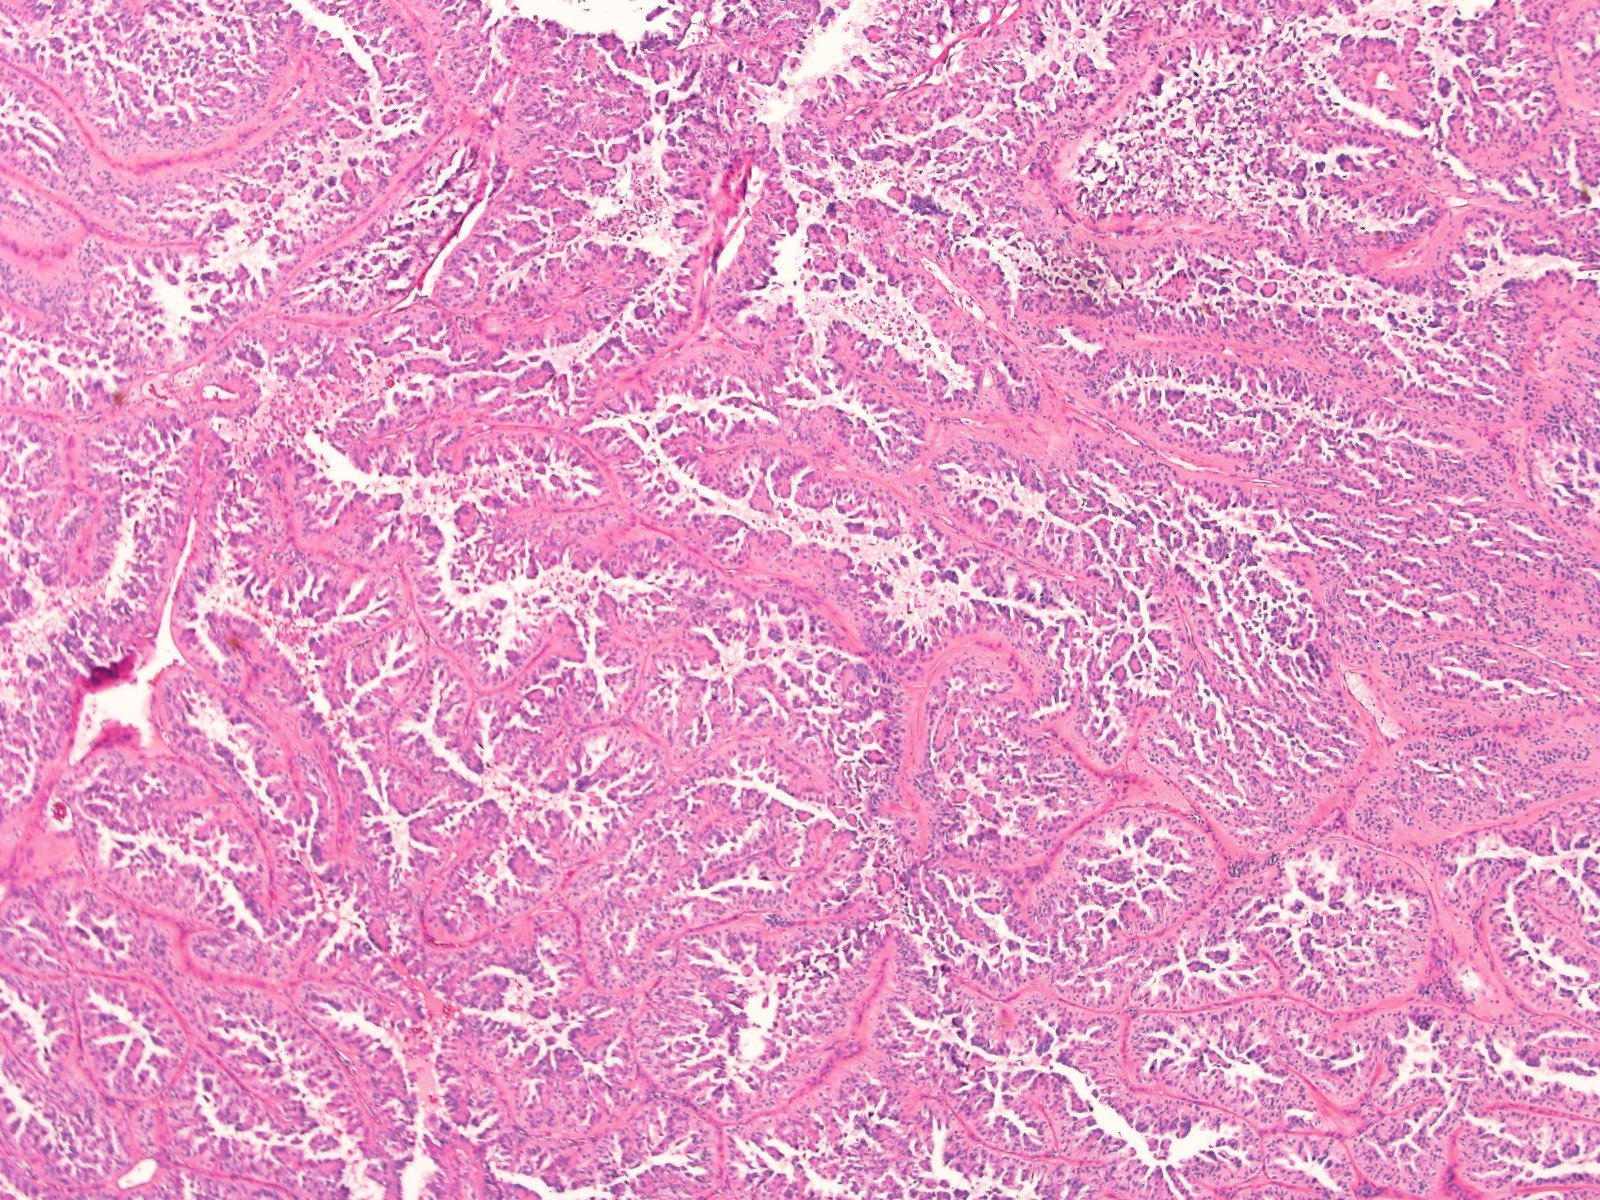

Renal tumor grading

Case ID: 839